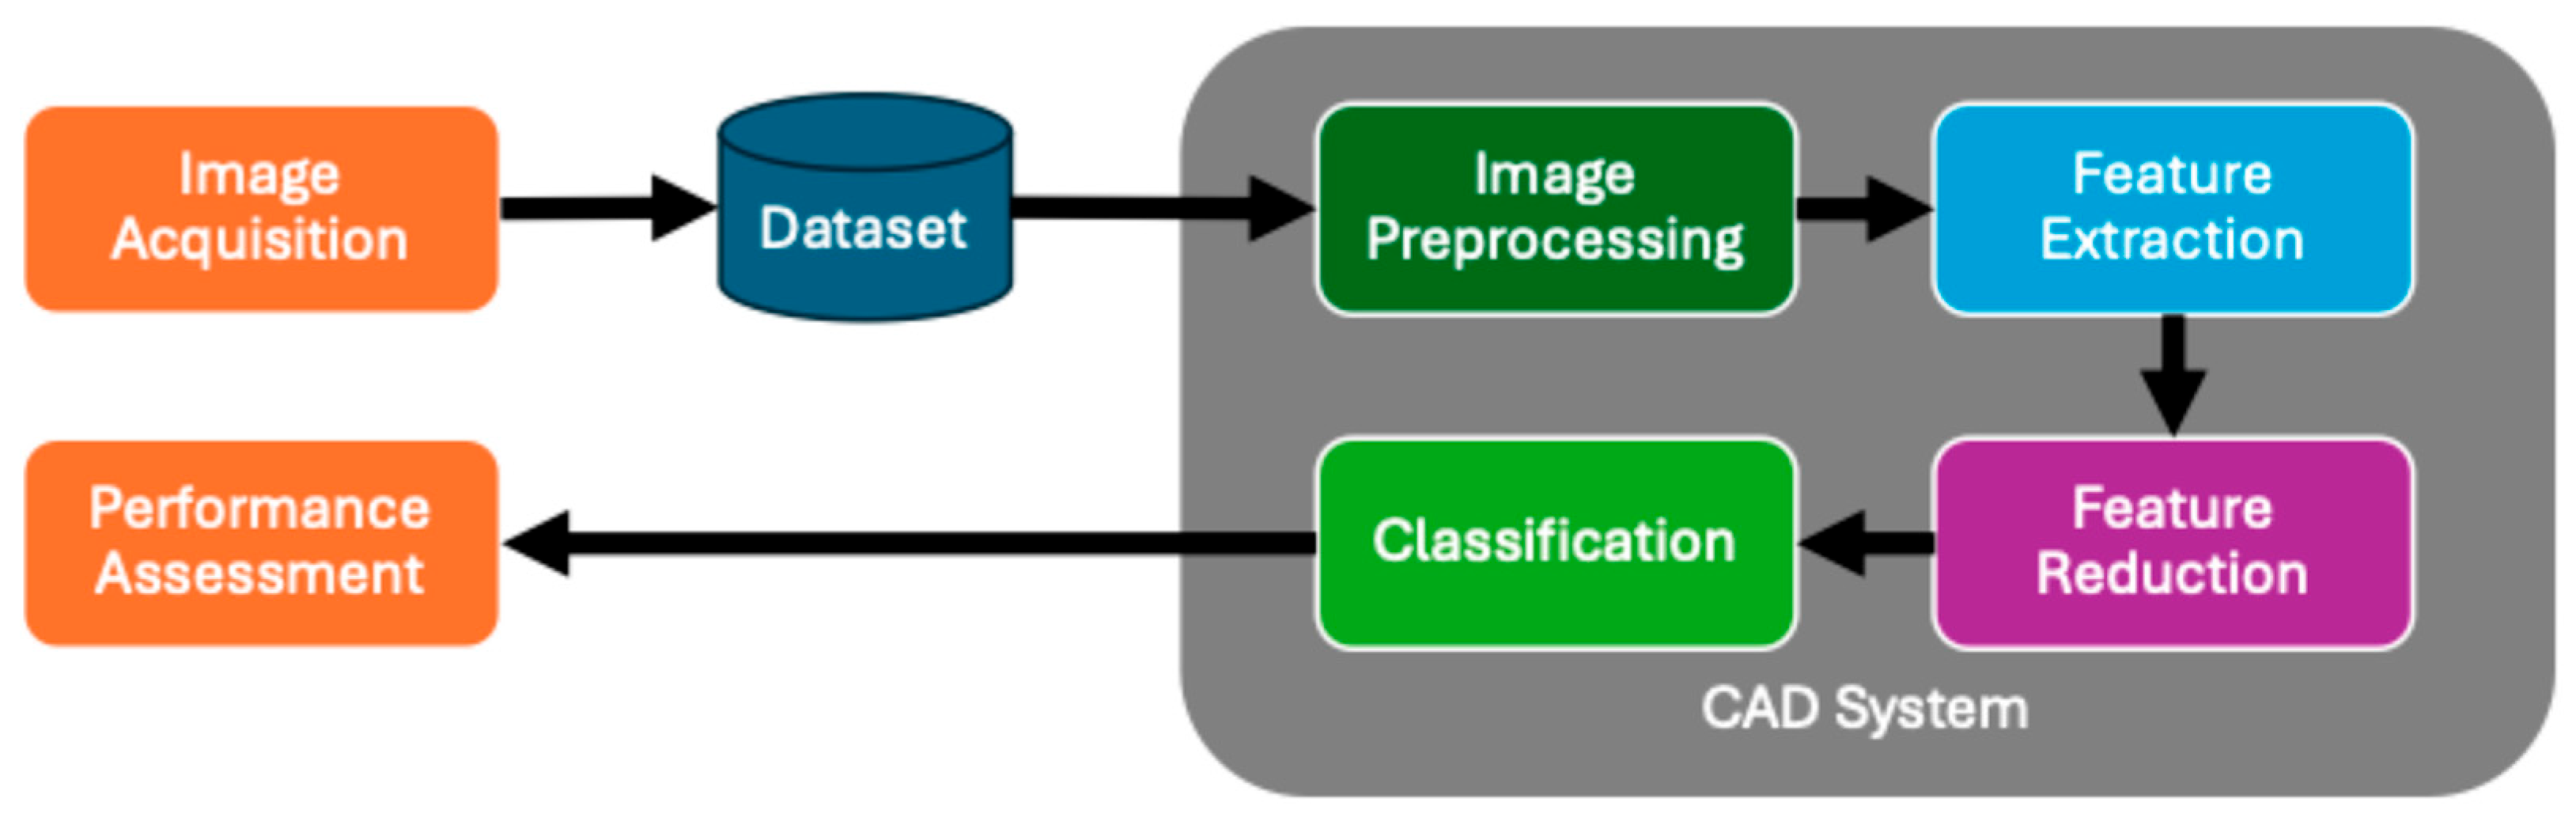

2. Computer-Aided Diagnosis System Architecture